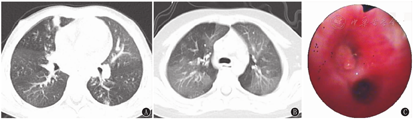

67例患儿胸部高分辨CT均表现为树芽征、小叶中心结节。19例(28.4%)并少量胸腔积液;22例(32.8%)并少量肺实变或不张;单侧病变22例(32.8%),双侧45例(67.2%);累及单个肺叶6例(9.0%),累及2个肺叶23例(34.3%),累及≥3个肺叶38例(56.7%),其中累及3个肺叶20例(29.9%)、4个肺叶12例(17.9%)、5个肺叶6例(9.0%)(图1A和图2A)。

35例(52.2%)患儿支气管镜下特点:71.4%(25/35例)表现为白色絮状、条索状分泌物(图1C);17.1%(6/35例)表现为黏液栓堵塞管腔(图2C),其中33.3%(2/6例)为塑型性分泌物,33.3%(2/6例)为塑型性分泌物合并远端通气不良,33.3%(2/6例)合并肉芽组织增生(图2C);10.9%(4/35例)表现为结节样凸起合并肉芽组织增生。

胸部高分辨CT是诊断细支气管炎的主要依据,包括直接征象和间接征象两大类特征性影像。细支气管扩张征(细支气管壁增厚和管腔扩张所致)、树芽征和小叶中心结节为直接征象,马赛克征及气体滞留征为间接征象[16]。本研究67例患儿胸部高分辨CT均表现为树芽征、小叶中心结节,部分合并少量胸腔积液(28.4%),当病变累及肺泡及其周围组织时,可出现肺实变或不张(32.8%)。肺部以双侧弥漫性病变为主(双侧病变45例,≥3个肺叶者38例),也可呈单侧局灶病变或弥漫性病变(单侧病变22例,单个肺叶者6例)。